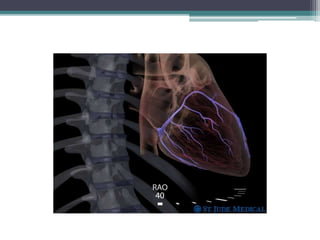

Angiographic views

• Right anterior oblique: (RAO) 48+/-7

projection,

▫ the fluoroscope beam is parallel to the CS plane ,

▫ the CS ostium is visualized ‘‘en face,’’ and the CS

guiding catheter is straight.